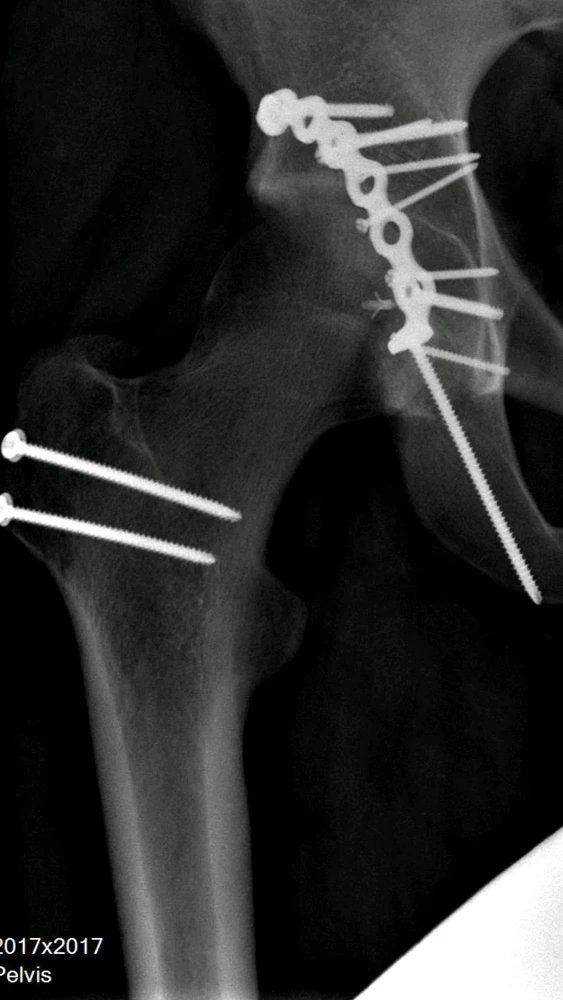

Pretty cool that I can still walk, run and jump after all this